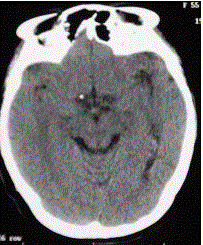

问题 患者男,20岁,癫痫病史。头部CT显示如下图。 可能的诊断为(提示进一步MRI检查如下图。)

选项 A.海绵状血管瘤 B.动静脉畸形 C.发育性静脉畸形 D.发育性静脉畸形伴海绵状血管瘤 E.脑梗死 F.脑出血

答案 B